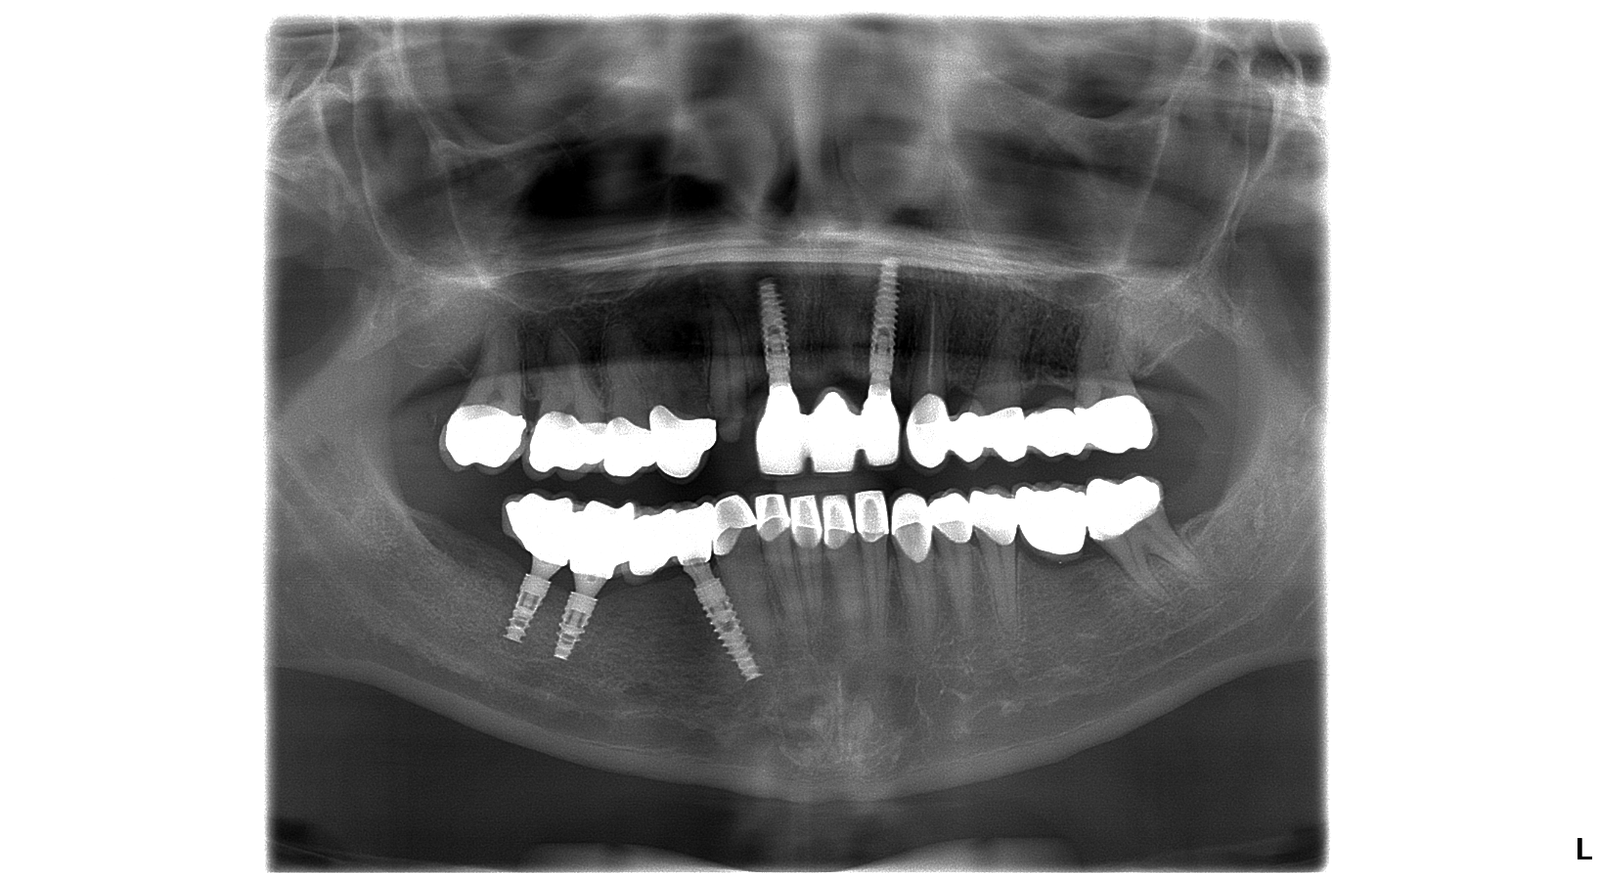

Snímok po ošetrení

Natália túžila mať dokonalé zuby a dokonalý úsmev. Rozhodla sa podstúpiť radikálnu zmenu. Jej ošetrenie zahŕňalo dve extrakcie, päť zubných implantátov, sedem implantových koruniek, pätnásť celokeramických koruniek, päť kovokeramických koruniek.